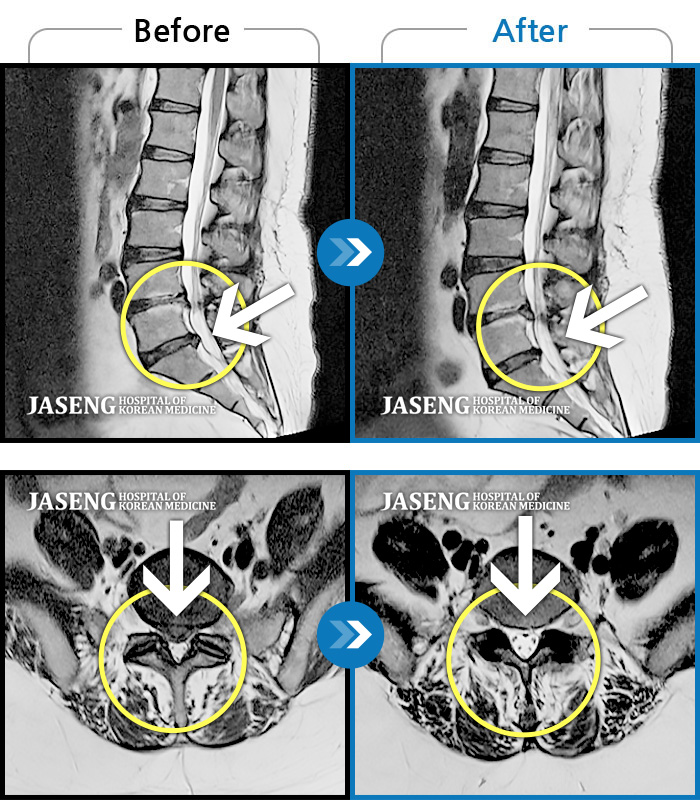

Before

After

환자에게 사전 동의를 받아 동일 조건에서 촬영되었습니다.

개인에 따라 치료 후 부작용이 발생할 수 있으니 의료진과 상담 후 치료를 진행하시기 바랍니다.

허리통증 및 우측 하지 저림과 근력 저하